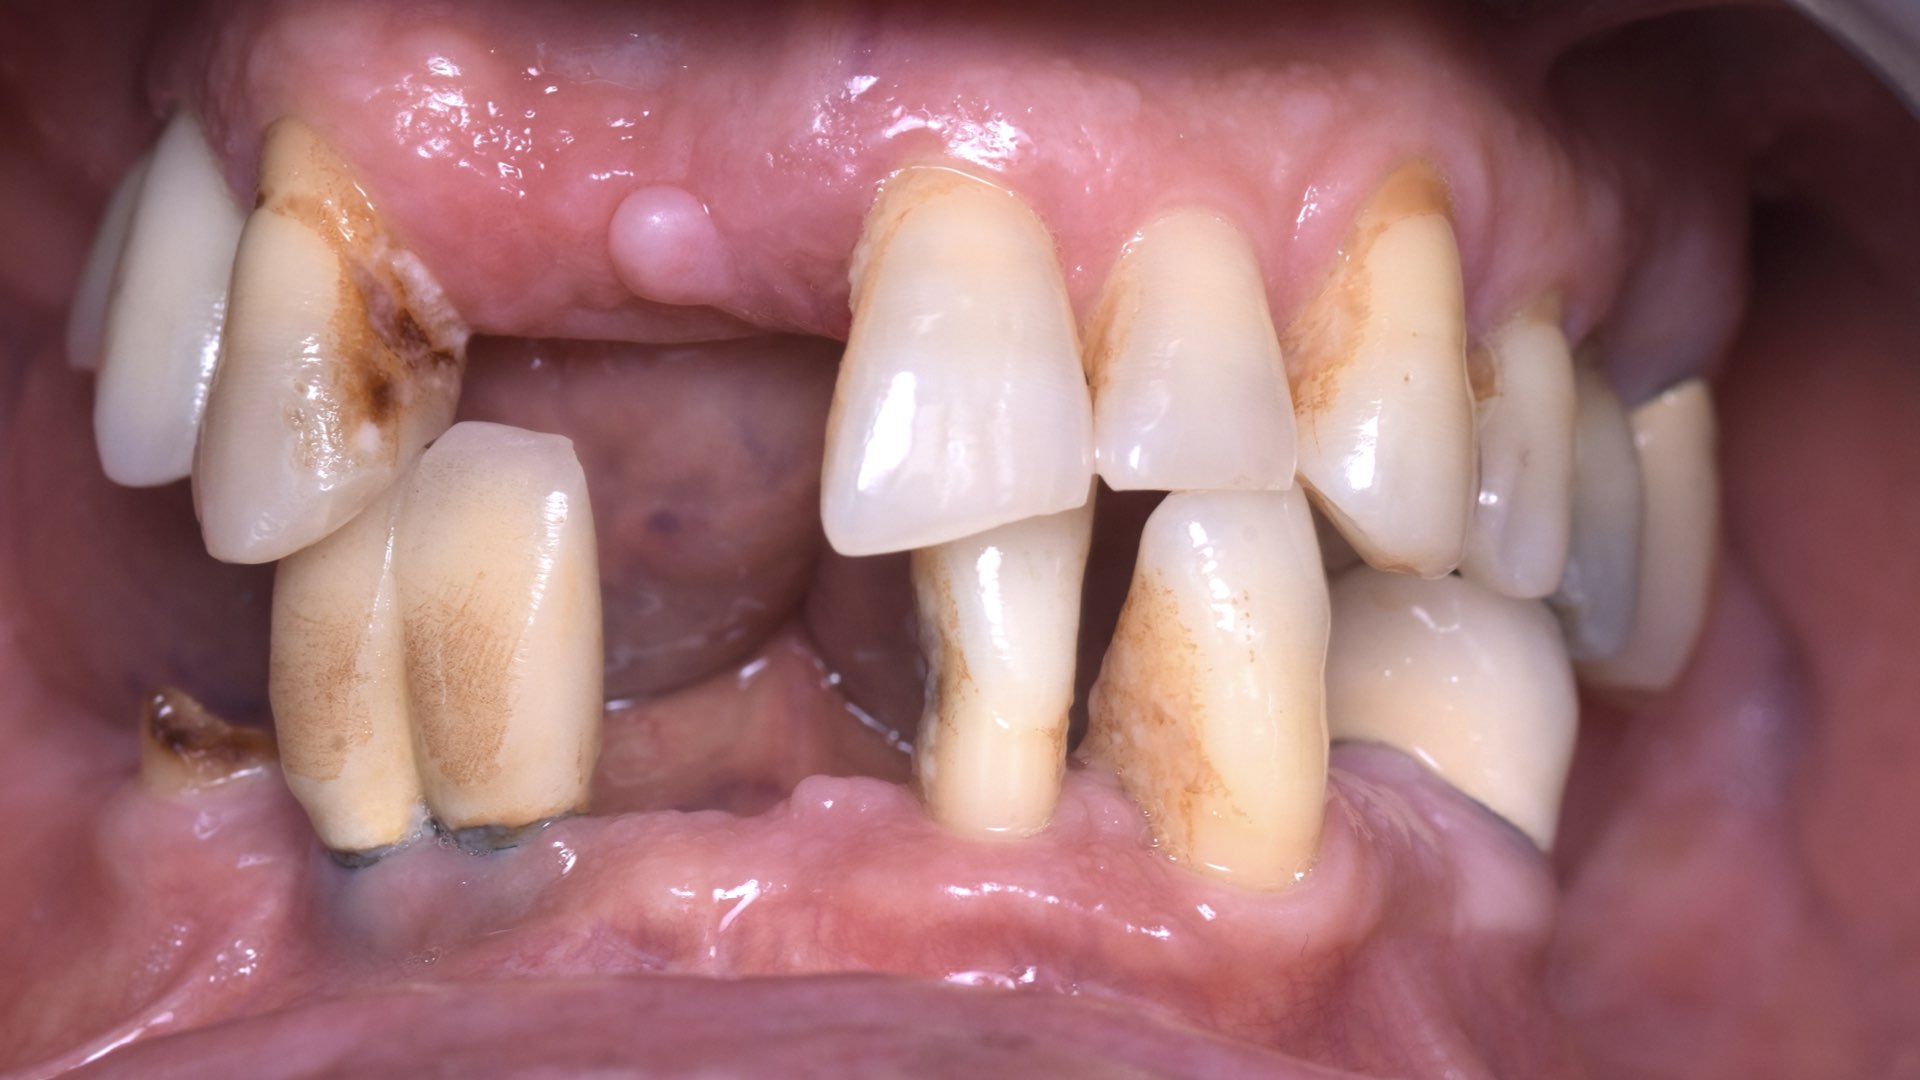

Les deux implants antérieurs seront tout d’abord posés afin de respecter un positionnement idéal pour un futur vissage palatin de la prothèse, puis les deux implants postérieurs seront inclinés à 20 degrés (protocole classique décrit par le Dr Malo).4 Ensuite des piliers coniques multi-unit droits en antérieur et de 17 degrés en postérieurs, sont vissés sur nos implants. Enfin les scan bodies sont placés avant les sutures, afin d’assurer un contrôle visuel de leur bonne position, ainsi qu’une bonne adaptation.